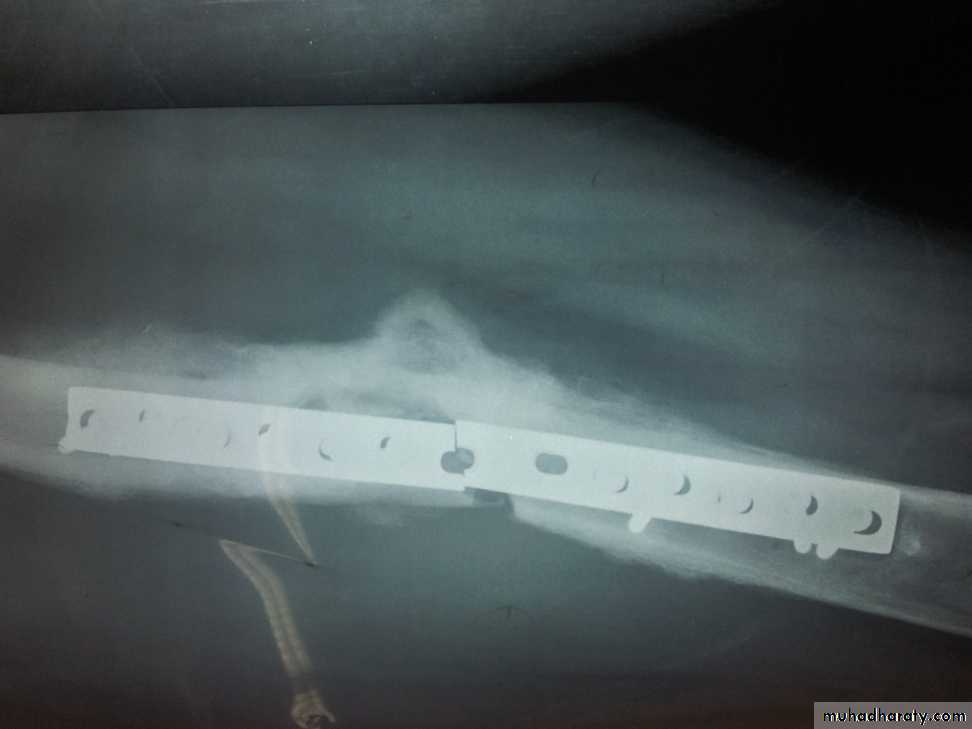

• Post traumatic and post operative osteomyelitis.

• 1)Post traumatic osteomyelitis.

• An open fracture may become infected

• It is the usual cause of acute osteomyelitis in adult.

• Treatment: The wound should be left open for inspection and frequent dressing, and then delayed primary closure after few days. The fracture is fixed by external fixator.

• There is an increased risk with the use of foreign material (metal, plastics) for internal fixation or joint replacement.

Chronic Osteomyelitis

It is used to be a sequel of acute haemtogenous infection, but now it is more frequently follows open fracture or postoperative complication.Pathology:

There is destruction of bone that follows acute infection leaving sequestra surrounded by dense sclerotic bone.

The imprisoned sequestra provoke a chronic seropurulent discharge, that escape through a sinus. Bacteria may remain dormant for years giving rise to recurrent flare of acute infection.

Imaging:

X-Ray: shows area of rarefaction surrounded by sclerosis.

And sometimes with sequestra.